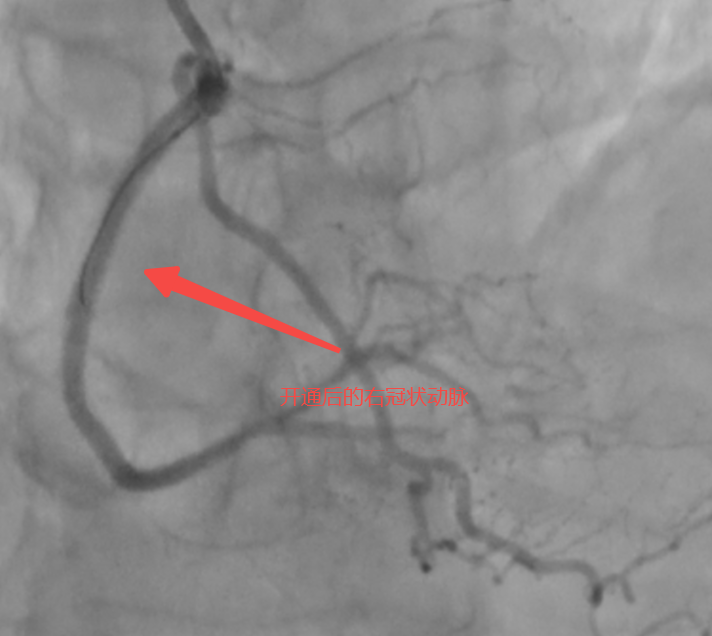

57歲的患者張先生(化名)近1年以來反復(fù)出現(xiàn)胸悶癥狀,經(jīng)當(dāng)?shù)蒯t(yī)院檢查后被診斷為“慢性完全閉塞病變(CTO)”,心臟處三根大血管發(fā)生嚴(yán)重病變,其中很重要的一根血管(右冠脈)完全堵死,還長滿“硬石頭”般的鈣化斑塊。當(dāng)?shù)蒯t(yī)院反復(fù)嘗試介入治療,均未成功打通血管,且評(píng)估認(rèn)為開胸搭橋的效果也不理想。不愿意接受開胸手術(shù)的張先生,慕名來到泰康同濟(jì)(武漢)醫(yī)院心血管內(nèi)科就診。

術(shù)中,馬志強(qiáng)主任團(tuán)隊(duì)啟用三維冠脈造影精準(zhǔn)定位側(cè)支路徑,以頭發(fā)絲般纖細(xì)的導(dǎo)絲,在側(cè)支血管中實(shí)現(xiàn)“毫米級(jí)”推進(jìn),成功建立逆向通路。隨后通過多項(xiàng)正向、逆向技術(shù)成功打通血管并植入藥物支架,恢復(fù)右冠脈血流。術(shù)后患者胸悶癥狀緩解,次日即可下床活動(dòng),目前已順利出院。